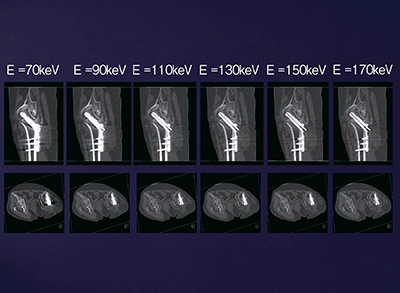

金属アーチファクトの軽減に用いられるmonoenergetic image(monochromatic image,仮想単色X線画像)は,80kVと140kVの画像から任意のエネルギー(40〜190keV)に相当する仮想的なイメージを作成する技術である。金属アーチファクトは,金属を通過する際に高エネルギー成分が残り,低エネルギー成分を吸収(ビームハードニング)することで生じるが,monoenergetic imageによって大幅に軽減することができる。通常,100〜140keVが良好であるが,syngo.viaではスライディングバーで画像を動かしながら,アーチファクトの少ない最適なエネルギーでの画像を確認し,リアルタイムに診断することができる。

症例1は,60歳代,女性,大腿骨頸部骨折。かなり厚い金属プレートで骨折部位が固定されているが,その骨癒合の状態の評価のためにDual Energy CTが施行された。撮影パラメータを図3に示す。monoenergetic image(図4a)では,金属アーチファクトが大幅に軽減した画像が得られ,自動作成される3D画像(図4b)と併せて診断可能である。

図5は,syngo.viaで表示されるmonoenergetic imageである。実際には1keVごとに表示されるため,その中から最も評価しやすい画像を選択する。患者がリハビリに移行するタイミングの評価などにきわめて有用である。

図5 症例1:monoenergetic image における

keVと金属アーチファクト軽減の関係